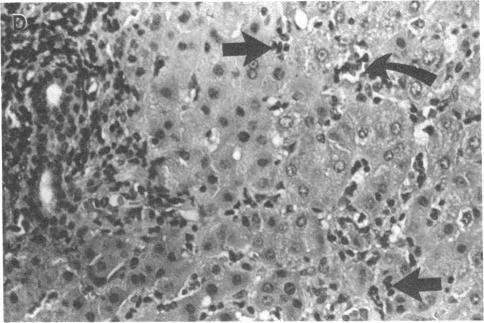

We have reported that clonal cells derived from Hep G2 cells transfected with a plasmid containing hepatitis B virus (HBV) DNA secrete spherical and filamentous forms of hepatitis B surface antigen (HBsAg), core particles, and virions into the culture medium. Here we describe the development of typical hepatitis in two chimpanzees following intravenous inoculation with the medium in which the transfected cells had grown. The liver biopsies from these animals showed characteristic lesions in parenchyma and portal tracts, more conspicuous at an earlier time in the chimpanzee that had received a greater number of virions. The amount of HBsAg in the serum of one infected chimpanzee increased with time after the initial inoculation and then decreased concomitantly with the appearance of antibodies against HBsAg and core antigens. HBsAg remained detectable in the other animal throughout the course of the experiment. The levels of hepatitis B "e" antigen in both animals peaked at week 5, signifying the acute phase of the infection. The activities of serum enzymes that are markers for necroinflammation also increased. The hepatitis HBsAg subtype of the virions isolated from the patient whose DNA was cloned and then used for transfection of the Hep G2 cells was the same as that found in the chimpanzees. Furthermore, the restriction enzyme analysis of the viral DNA isolated from the chimpanzees was identical to the cloned DNA. Thus, HBV DNA-transfected Hep G2 cells can support the replication of virions that, in turn, produce hepatitis in chimpanzees.

我们曾报道,用含乙型肝炎病毒(HBV)DNA的质粒转染Hep G2细胞后获得的克隆细胞,可将球形和丝状的乙型肝炎表面抗原(HBsAg)、核心颗粒及病毒粒子分泌到培养基中。在此,我们描述了两只黑猩猩经静脉接种转染细胞生长过的培养基后出现典型肝炎的情况。这些动物的肝脏活检显示,实质和汇管区有特征性病变,在接种较多病毒粒子的黑猩猩中,病变在早期更为明显。一只受感染黑猩猩血清中的HBsAg量在初次接种后随时间增加,随后随着抗HBsAg和核心抗原抗体的出现而下降。在整个实验过程中,另一只动物的HBsAg始终可检测到。两只动物的乙型肝炎“e”抗原水平在第5周达到峰值,表明处于感染急性期。作为坏死性炎症标志物的血清酶活性也升高。从其DNA被克隆并用于转染Hep G2细胞的患者体内分离出的病毒粒子的HBsAg亚型,与在黑猩猩中发现的相同。此外,从黑猩猩中分离出的病毒DNA的限制性酶切分析与克隆DNA相同。因此,HBV DNA转染的Hep G2细胞能够支持病毒粒子的复制,而这些病毒粒子反过来会在黑猩猩中引发肝炎。